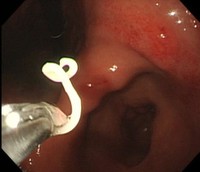

治療の第一選択は、内視鏡による摘出ですが、内視鏡は必要ないとの報告もあります。アレルギーを抑える注射と香蘇散という漢方薬で、ほとんどのアニサキス症を治療できるとの報告を見たことがあります。ただ、私は、万全を期すため一般的な内視鏡による摘出を第一選択としたいと思っています。